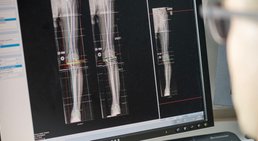

Meine jahrelange chirurgische Erfahrung umfasst sowohl den Bereich der Endoprothetik als auch mein Spezialgebiet der Fußchirurgie.

In der Hüft-, Knie- und Sprunggelenksendoprothetik kann ich daher auf den aktuellsten Stand der Wissenschaft zur Therapieoptimierung zurückgreifen.